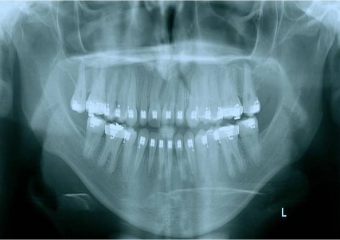

Rx inicial - Clínica Cliniface

Rx inicial